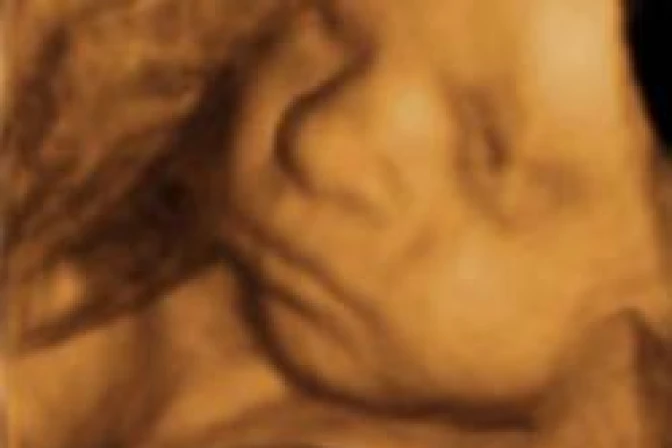

La ley señala que un médico debe realizar un ultrasonido 24 horas antes de un aborto, excepto en casos de emergencia médica, y mostrar la imagen a la madre, haciéndole escuchar los latidos del corazón del feto.

Sin embargo, la mujer puede optar por no ver la imagen o escuchar los latidos. Para ello deberá firmar una declaración antes de que se le realice el sonograma.